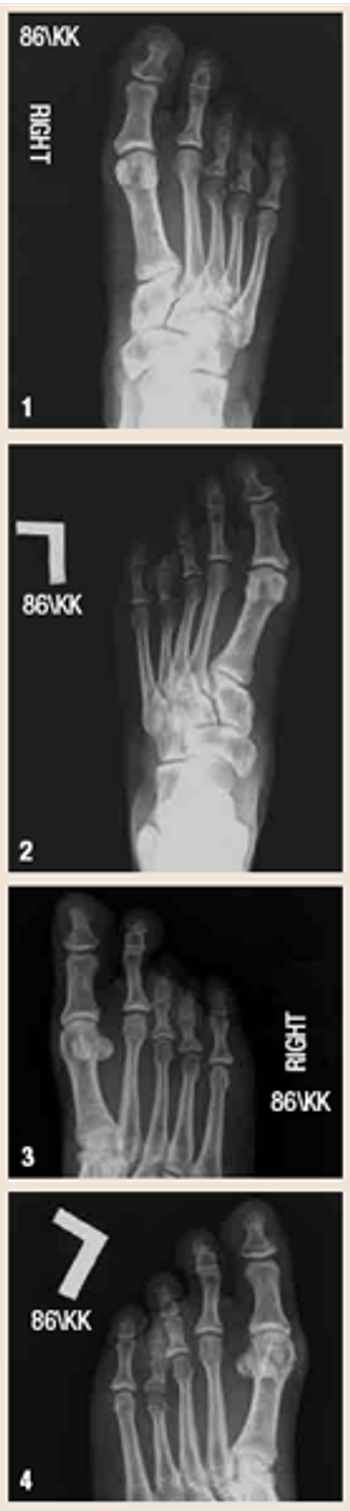

This 41-year-old woman presented with a known history of bilateral foot deformities and new complaints of bilateral foot pain. She had associated hallux valgus deformities.